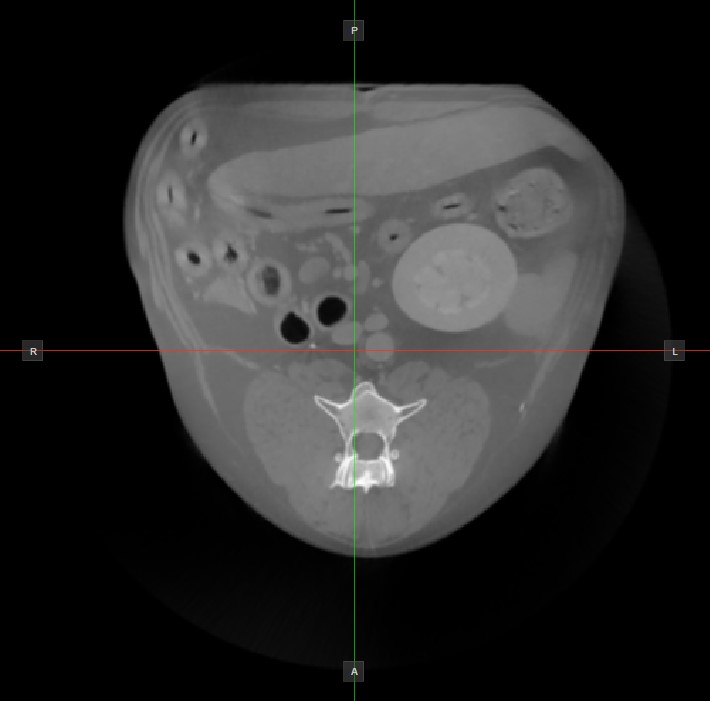

Image Orientation and Image Planes¶

The position and intersection of the other two image planes not represented in the active viewport is indicated by two vertical and horizontal lines called slicers. The endpoints of each slicer are labeled with a letter that corresponds to the appropriate direction/side of the 3D volume, based on the RAS coordinate system.

Only four sides of the available six are indicated on each 2D viewport. The labels and the corresponding side are the following:

Patient Right (R), indicating the right side of the body

Patient Left (L), indicating the left side of the body

Anterior (A), indicating the front side of the body

Posterior (P), indicating the back side of the body

Superior (S), indicating the top side of the body

Inferior (I), indicating the bottom side of the body